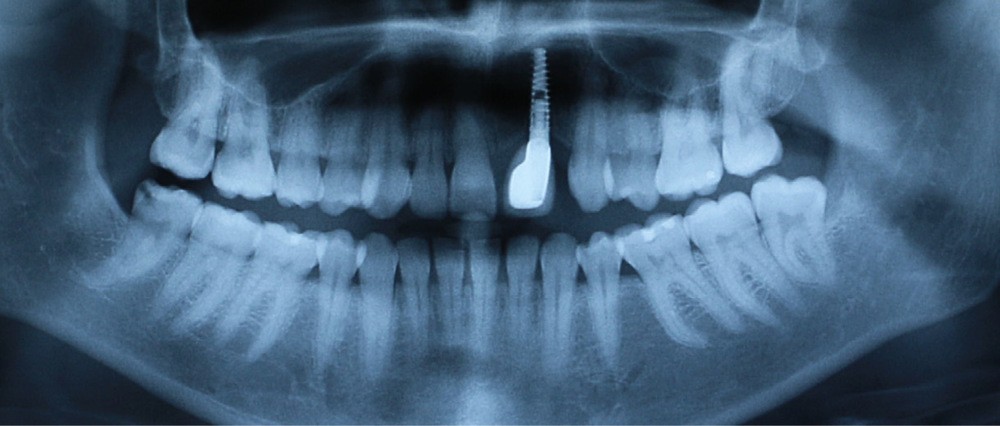

À la suite d’un accident de la voie publique il y a plusieurs années, le secteur antérieur maxillaire a été traumatisé, 21 et 22 ont été expulsées, et 11 et 12 présentent d’importantes résorptions radiculaires externes inflammatoires visibles à la radiographie panoramique (fig. 1).

- au niveau dentaire : une arcade maxillaire asymétrique avec déviation du milieu maxillaire à gauche. On note l’absence de 21, 22, 25, 35 et 45, une classe II droite et gauche avec infraclusion antérieure et la présence d’un implant en place de 21 avec un diastème de 3 mm entre 21 et 23 (fig. 3) ;

- le rétablissement d’une occlusion engrenante et symétrique en classe I. L’extraction de la 15 permettra, en l’absence des trois autres deuxièmes prémolaires, de symétriser l’arcade, de rétablir une occlusion de classe I et d’apporter l’espace nécessaire au recentrage du milieu maxillaire ;

- la fermeture de l’espace de 25 et la réouverture de l’espace pour un implant en place de 22.